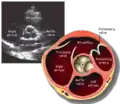

Parasternal short axis (PSAX)

This view is obtained in the same window as the parasternal long, but with the probe rotated 90°. In this view, the aortic valve is seen in cross-section with the right ventricular inflow & outflow tracts visible with the tricuspid valve as well. Pulmonary valve is not visible in this view. Both the right and left atria are visible.

The standard PSAX view is at the level of the aortic valve, but moving the probe along the long-axis can review the LV outflow tract, LV at the base, and LV at the midsection.

Structures visible:

- Aortic valve in short-axis

- Aortic valve dysfunction, aortic sclerosis/stenosis

- Tricuspid valve in long-axis

- Pulmonary valve in long-axis

- Right ventricle, including inflow and outflow tracts

- Left ventricle in short-axis

- Closer to the base can reveal the left ventricular outflow tract

- At the level of the base can show the movement of the mitral valve leaflets in short-axis

- At the level of mid-LV can show papillary muscles

Measurements in this view can be used to quantify the heart:

- Aortic valve area by planimetry

- Color doppler of all four valves

- Spectral doppler of tricuspid and pulmonary valves